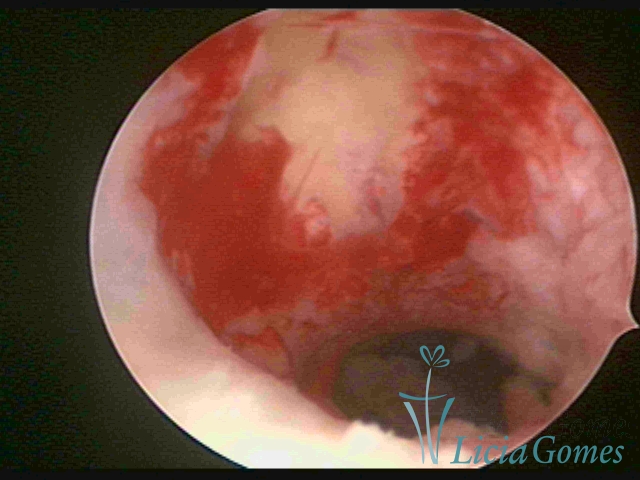

Retraction of a cesarean section scar with a non-absorbable suture for 30 years.

Retraction of a cesarean section scar with a non-absorbable suture for 30 years panoramic view